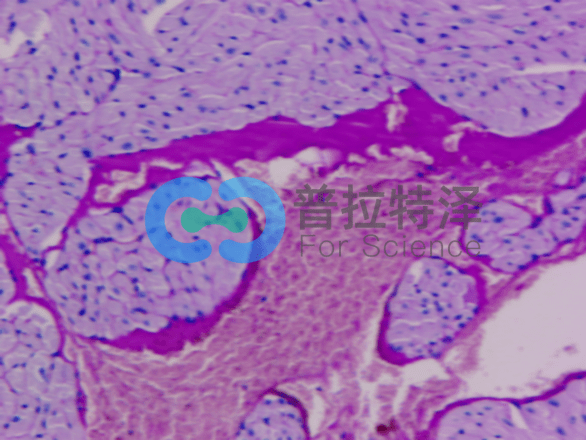

PAS染色結果解讀由普拉特澤生物給大家解答與分享,PAS染色(過碘酸雪夫染色)是一種重要的組織化學染色方法,廣泛應用于病理診斷和科研實驗。通過特定的化學反應,使組織中的多糖類物質呈現出特殊的顏色,從而揭示其結構和功能狀態。普拉特澤生物組織染色檢測平臺可承接各種病理染色外包服務,包括HE染色

油紅O染色Masson染色等實驗外包服務,本文將詳細解讀PAS染色的結果,幫助科研小白更好地理解這一技術及其應用。

[圖1]

首先,我們需要了解PAS染色的基本原理——過碘酸能夠氧化組織中的多糖類物質,使其形成醛基或酮基。隨后,雪夫試劑與這些醛基或酮基發生反應,生成不溶于水的有色化合物,從而在顯微鏡下呈現出特定的顏色。這種顏色反應不僅具有高度的特異性,而且敏感性也很高,能夠準確反映組織中多糖類物質的分布和含量。

染色強度的深淺可以反映組織中多糖類物質的含量。一般來說,染色越深,說明多糖類物質含量越高;反之,染色越淺,則含量越低。同時,我們還需觀察染色的分布情況,以了解多糖類物質在組織中的具體位置和形態。